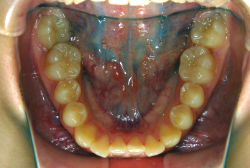

混合歯列期から治療開始した側方拡大による非抜歯症例

「配列の凸凹を治したい」という主訴で来院したケースです。診断の結果、永久歯がすべて生えそろうと、かなり厳しい叢生(歯並びの凸凹のことです)になる可能性が高いと判明しました。原因としては特に上の顎の骨が小さいため、歯を収容する容量不足になっていると診断しました。このケースの場合は、成長発育期に治療開始しますので、顎の骨を土台ごと大きくすることが可能です。

そこで、まず急速拡大装置を使用して上顎骨の拡大を行い、上顎骨の容量が拡大したことを確認後、マルチブラケット装置を使って全体の修正をする、と言う二段階の作戦をとることになりました。

この時期に使う急速拡大装置は、適切な診断に基づいて正しく使用することで確実に骨を大きくすることができます。拡大することで隙間が確保できるので、永久歯の抜歯を避けることができます。

急速拡大装置を1日1回装置の中央にある拡大ネジを、ご自身で回して頂くことで25日間くらいかけて、6mmほど拡大しました。拡大後は、上顎の前歯の隙間が広がっていることがお分かりいただけると思うのですが、土台の骨ごと広がるのでこのような隙間ができます。その後1年半くらいマルチブラケット装置を使用して、全体の修正を行いました。